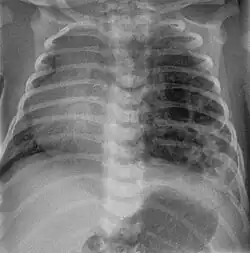

| Left tension pneumothorax with a large, well-demarcated area devoid of lung markings with tracheal deviation and movement of the heart away from the affected side. |

Tension pneumothorax

Tension pneumothorax is an emergent condition in which air gets trapped in the space between the chest wall and the lung. This space is referred to as the pleural space. Because air can't escape from this space, the air pocket grows larger and larger, resulting in the lung collapse closest to the pneumothorax. Forces are transmitted to the mediastinum and effectively "push" the mediastinal structures to the opposite side of the chest.[5]